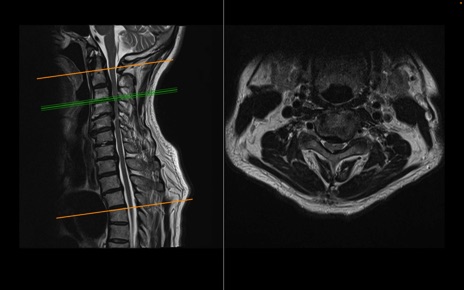

頚椎MRI

T2WI(横断像)

T2WI(矢状断像)